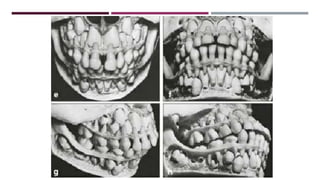

• #22 At 2 ½ year of age, deciduous second molars usually have reached the occlusion and deciduous dentition is complete. Between 2 ½ and 5 years of age, a very miniminal change is position is seen. A and b: both arches have half round form C : opposing incisors have no contact in habitual occlusion. Vertical overjet varies between 0-2mm. Teeth are oriented almost perpendicular to the occlusal plane D: the succedaneous tooth are at the same level except for canines.

• #55 Maxillary teeth arranged in arch with diastema between centrals. Four maxillary incisors contact with six mandibular teeth Mandibular arch with fewer diastema except distal to deciduous canines n which maxillary canines fit There is less room for premolars and permanent canines in the maxilla than in the mandible. Second permanent molars distobuccally angulated in maxillary and mesiolingually angulated in mandibular

• #57 Skull at 8 years of age. Permanent incisors particulary maxillary centrals are large in comparison with rest of skull Incisors are labially inclined. Flush terminal plane hinders the intercuspation of permanent molars Maxillary permanent canines are located high, adjacent to piriform aperture. In the maxilla, only limited room is available for developing premolars and canines than mandible

• #58 The forming parts of central incisors are near the nasal floor and canines are near the roots of lateral incisors. No diastema in mandibular incisors and roots converge apically. Maxillary central incisors have completed eruption but not the lateral Crowns of permanent canines overlap first premolar vertically. While in mandible there is sufficient space between them